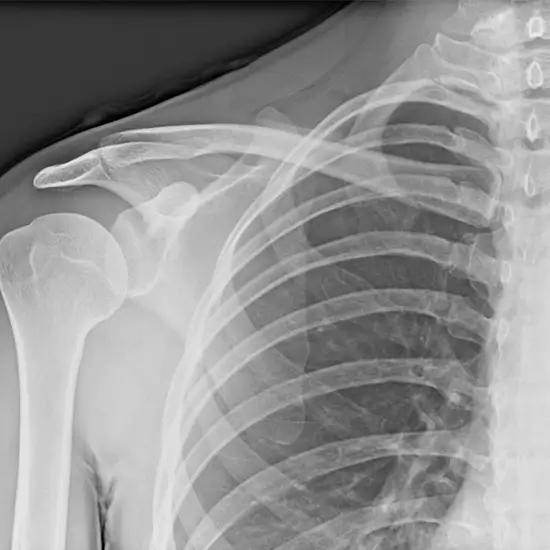

X-ray Right Shoulder Joint AP/Lateral

The shoulder includes the shoulder joint, collarbone, shoulder blade, upper arm bone, skin, and muscles. X-rays pass from front to rear in an Anterior-Posterior (AP) projection. The lateral perspective is patient-side. It visualizes upper arm, shoulder fractures/dislocations, bone tumors, arthritis, osteoporosis, and degenerative illnesses such as calcium deposits.